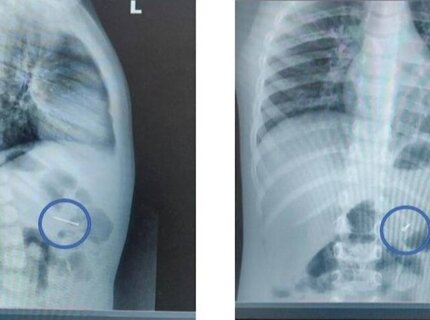

Подмосковные врачи спасли мальчика, проглотившего гвоздь